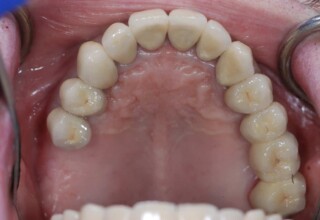

Εκτεταμένη αποκατάσταση με στεφάνες(θήκες) σχεδόν σε όλα τα δόντια λόγω εκτεταμένων αποτριβών, παλαιών αποκαταστάσεων, οπισθίων απονευρώσεων και αισθητικών προβλημάτων. Ο ασθενής(60 ετών) παρουσίαζε έντονο βρυγμό (τρίξιμο δοντιών) που δεν είχε αντιμετωπίσει ποτέ, με αποτέλεσμα μεγάλες αποτριβές που απειλούσαν την ακεραιότητα των οπισθίων δοντιών. Οι ανασυστάσεις(σφραγίσματα) των δοντιών έγιναν κυρίως με συγκολλούμενα ρητινώδη υλικά και τρεις χυτούς άξονες ψευδοκολοβώματα. Τοποθετήθηκαν προσωρινές στεφάνες όπου εκτιμήθηκε το επιθυμητό μέγεθος, το σχήμα και η θέση των δοντιών πριν κατασκευαστούν οι τελικές μόνιμες στεφάνες.